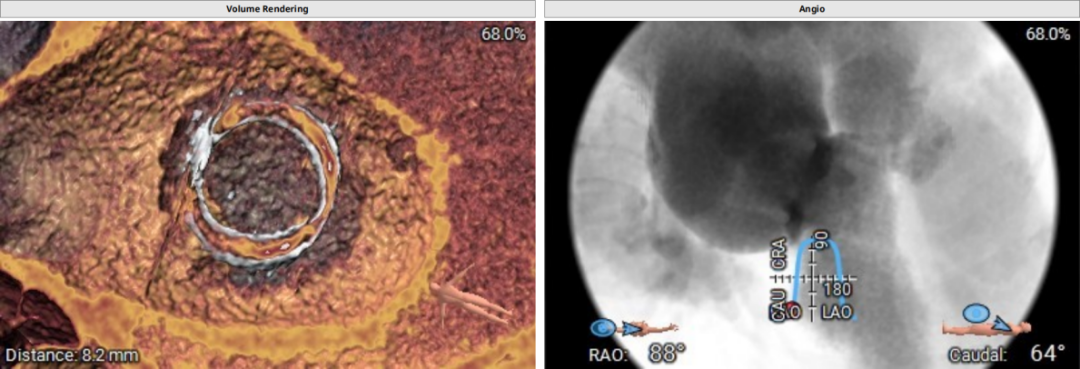

术前CT评估示:患者二尖瓣生物瓣置换术后,原生物瓣型号未知,生物瓣金属环平均内径25.9mm,外径31.5mm,瓣架高度15.9mm;

模拟27mm瓣膜植入情况:

主动脉-二尖瓣角度:102.3°;

术中建议造影角度:RAO 58°/CRA 44°;RAO 49°/CRA 62°。

释放定位件,确保定位件位于生物瓣瓣窦内,推送植入瓣膜至瓣环平面,打开瓣膜支架,支架释放后退出导管输送系统。

瓣膜定位